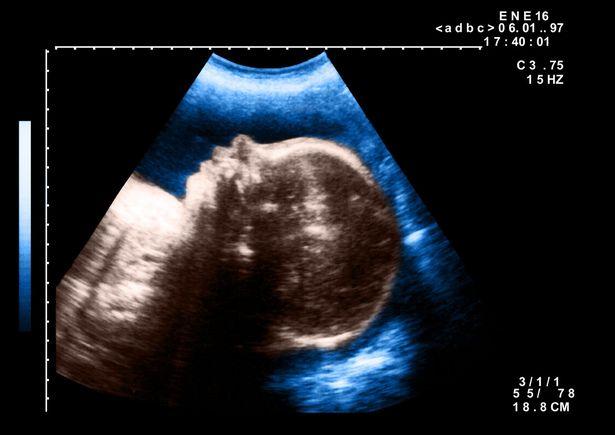

Topul celor mai rare anomalii genetice: de la bebelușul ciclop, la fetița sirenă, adolescentul-lup și tânărul închis într-un circ din cauza figurii înfricoșătoare Topul celor mai rare anomalii genetice: de la bebelușul ciclop, la fetița sirenă, adolescentul-lup și tânărul închis într-un circ din cauza figurii înfricoșătoare